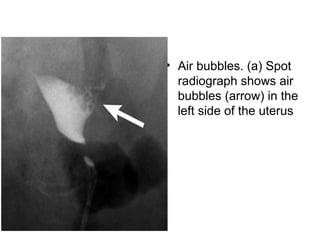

• Air bubbles.(a) Spot radiograph shows air bubbles (arrow) in the left side of the uterus

• Air bubbles. (a) Spot

radiograph shows air

bubbles (arrow) in the

left side of the uterus